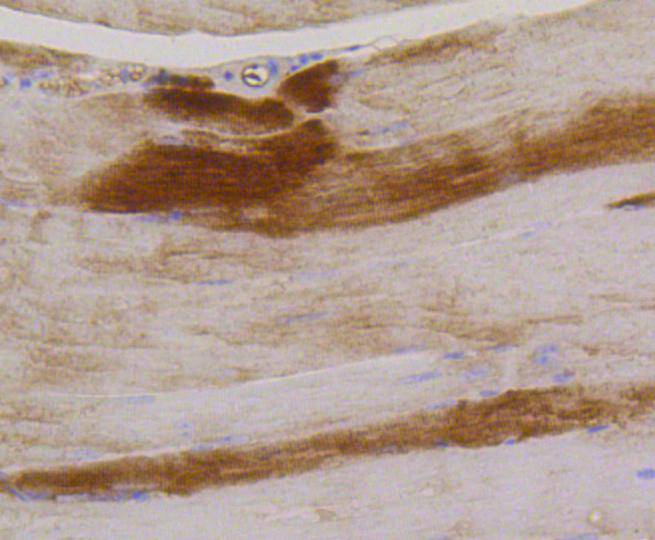

Immunohistochemical analysis of paraffin-embedded mouse skeletal muscle tissue using anti-Phospho-Glycogen synthase 1(S641) antibody. Counter stained with hematoxylin.